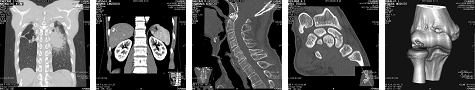

〇マルチスライスCT検査(64列)

*マルチスライスCT(64列)

・ 高速スキャンにて被爆線量を抑え、画像再構成にてあらゆる断面、3D画像、mm単位の薄い断面を作成することがきます。

・ CTでは頭・胸腹部検査をはじめ脊椎・四肢検査にも有効で、圧迫骨折・横突起骨折ミエロCTや手足の微小骨折(手足根骨)・骨癒合状態の確認・3D画像による病変の立体的把握にも有効です。

・ 造影剤CT撮影もおこなっております。